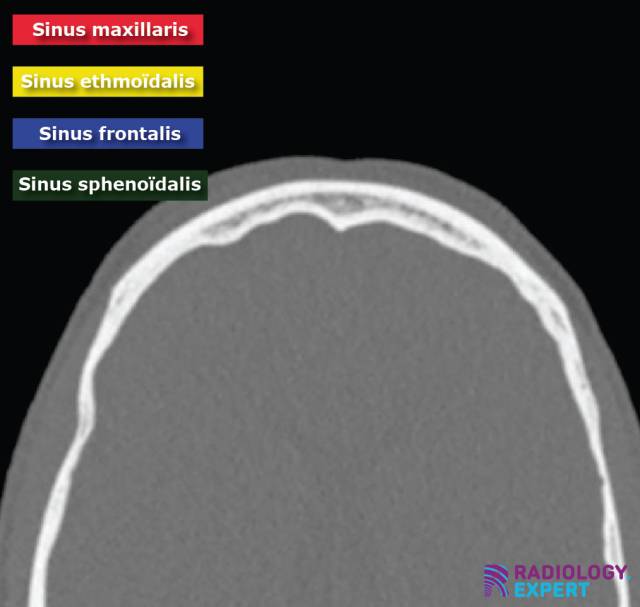

CT sinus

De basis principes van het CT sinus onderzoek.

Een CT onderzoek van de neus en paranasale sinussen is het radiologisch onderzoek van eerste keuze voor het in beeld brengen van ontstekingspathologie en benige afwijkingen. Het interpreteren van CT beelden van deze regio kan in het begin ingewikkeld zijn. Deze praktische module is speciaal ontworpen om je te helpen met een systematische beoordeling van het CT sinus onderzoek. De diepgaande leerstof is zowel relevant voor geneeskunde studenten als voor arts-assistenten die zich willen specialiseren in het KNO vakgebied.

Normale anatomie en veelvoorkomende pathologie komen uitgebreid aan bod (fig. 1). Daarbij is de module is niet alleen gericht op het herkennen van de normale anatomie, maar ook op het identificeren van klinisch relevante anatomische varianten die een rol spelen bij de pre-operatieve besluitvorming van endoscopische sinuschirurgie. De relatie met relevante vasculaire/neurologische anatomische structuren en een pre-operatieve CT checklist voor deze chirurgie wordt besproken.

• Paranasale sinussen: sinus maxillaris/ethmoïdalis/sphenoïdalis/frontalis

CT sinus normale sinussen